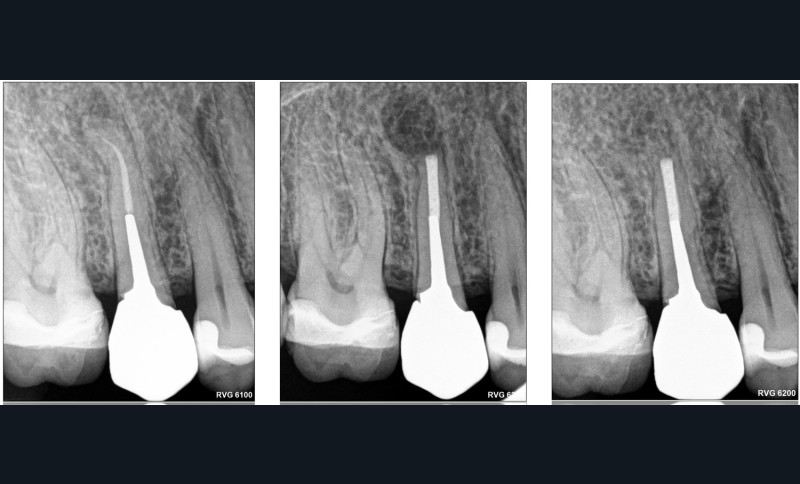

La chirurgie endodontique ne se limite pas à couper la racine mais consiste en un traitement endodontiquea retro. Comme pour le retraitement par voie orthograde, l’intervention peut intéresser un ou plusieurs canaux. L’imagerie est l’élément clé de la décision. Le CBCT (Cone Beam Computed Tomography) vient au service du sens clinique du praticien.